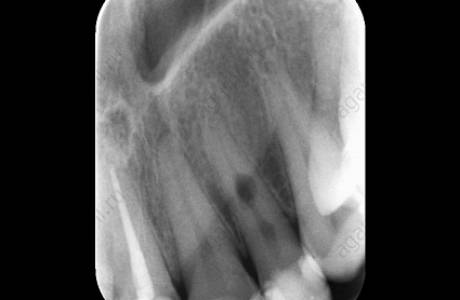

До лечения

Пациентка обратилась к врачу с острой болью. После изучения прицельного снимка обнаружилась резорбция (разрушение) корня с двумя гранулемами (участками воспаленной ткани).

После лечения

Как правило, такие зубы идут на удаление. В данном случае врач решила сохранить зуб. Было проведено эндодонтическое лечение, которое закончилось через несколько недель. Зуб пациентки сохранен.